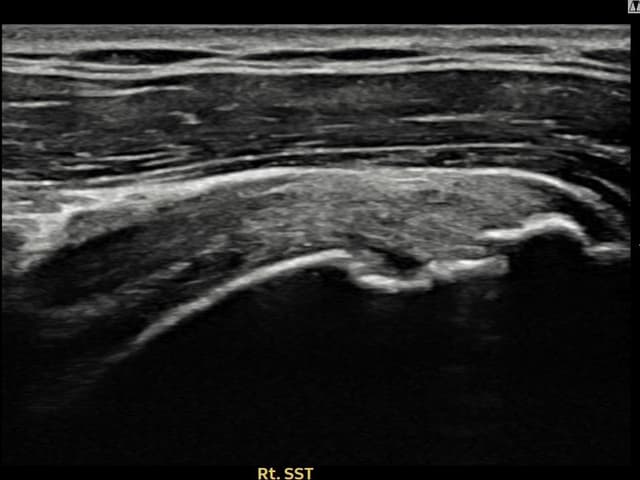

[촬영시기:22.09.19~22.12.09]

[어깨인대 축소봉합술] 우측 어깨 통증이 수개월간 지속되어 내원하셨습니다.